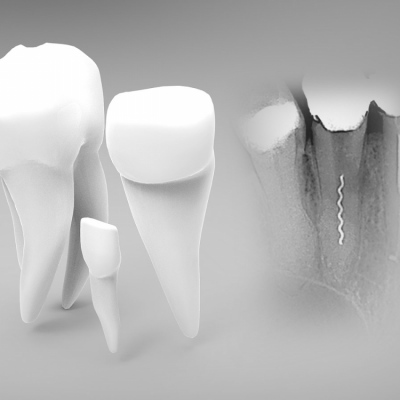

Implanty są śrubami wykonanymi z tytanu, będącego materiałem wysoce biokompatybilnym. W zabiegu wykorzystuje się zjawisko osteointegracji, które...

Podczas leczenia kanałowego, szczególnie kiedy opracowywane są zakrzywione kanały korzeniowe, może się zdarzyć, że używane narzędzie kanałowe...